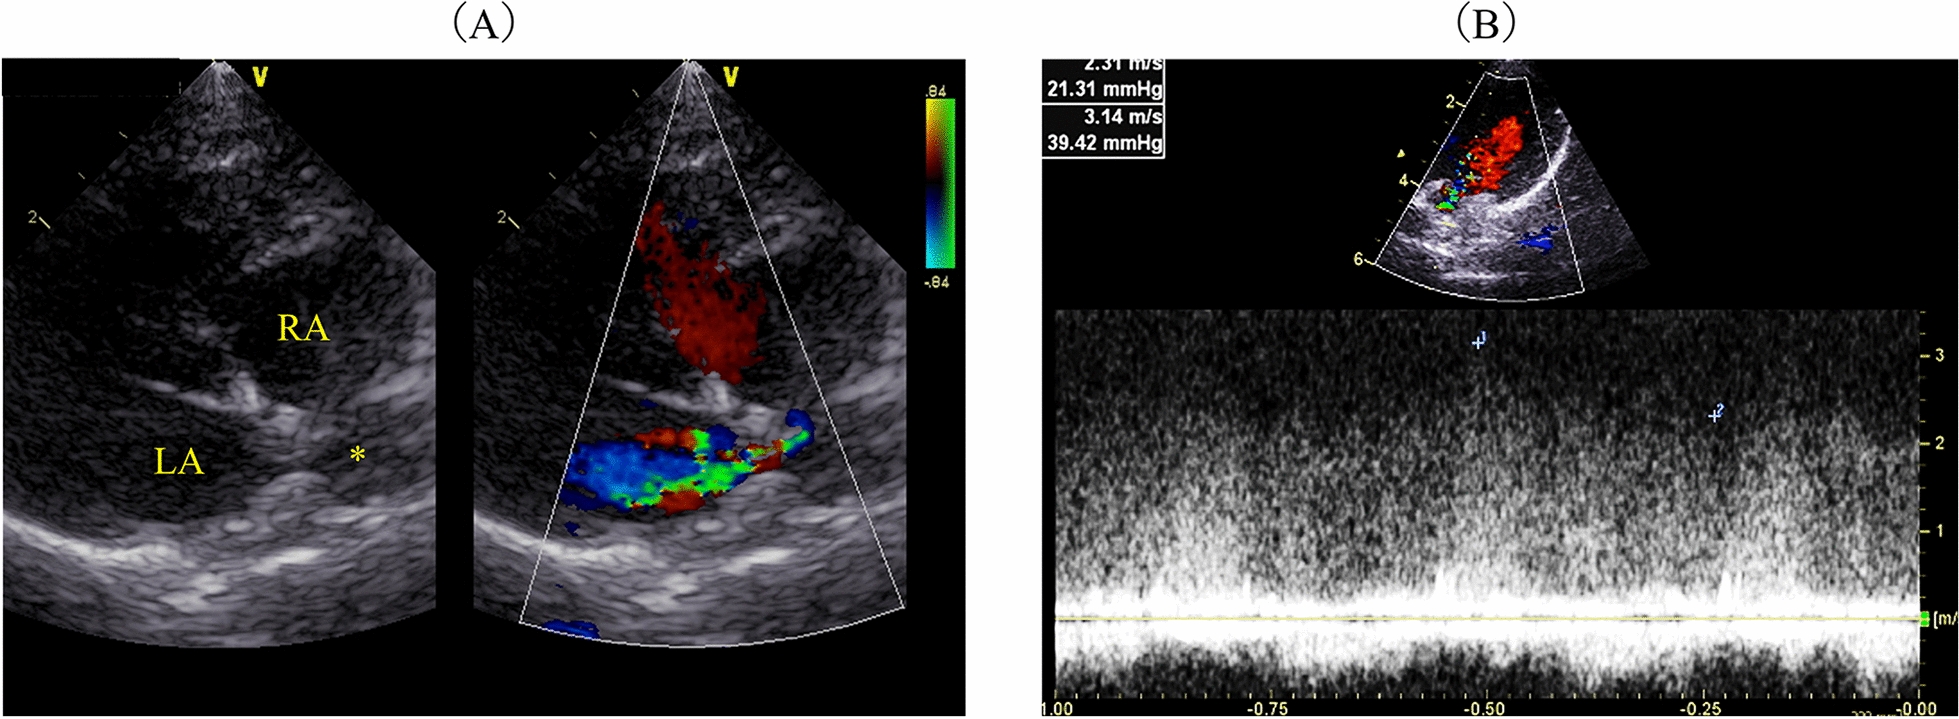

Case presentation: A 2 year-old Norwegian Forest cat was diagnosed with pulmonary oedema and PH secondary to cor triatriatum sinister (CTS) and showed improved breathing following two subcutaneous furosemide treatments, 1 and 2 mg/kg, during an overnight stay at the referral veterinary hospital. Sildenafil alone (0.69 mg/kg, PO, BID) was prescribed post-discharge to address PH without diuretics. Post-discharge from the referral veterinary hospital, collapse and pre-syncope were suspected to be due to PH. Consequently, sildenafil was titrated weekly, starting at 1.09 mg/kg BID and increasing to 1.63 mg/kg BID. Pre-syncope and collapse resolved, and pulmonary opacities reduced considerably, although concerns remained that increased pulmonary blood flow to suspected CTS from sildenafil might worsen cardiogenic pulmonary oedema. The patient was also treated with rivaroxaban (2.5 mg/head, SID), considering the increased risk of thrombus formation due to blood flow stasis and endothelial damage. Thirty-eight days later, the cat presented for the first time to our hosipital (Azabu University Veterinary Teaching Hospital) for examination. On echocardiography, a continuous mosaic blood flow (maximum and minimum velocity, 3.14 m/s; estimated pressure gradient, 39.4 mmHg) was observed in two enlarged pulmonary veins. Pulmonary artery enlargement (main pulmonary artery to thoracic aorta ratio: 1.90), pulmonary vein stenosis (PVS), and diffuse bilateral ground-glass lung opacities were observed using computed tomography. PH with unilateral PVS involving two out of the three right pulmonary veins, specifically the right cranial and right middle pulmonary veins, along with pulmonary parenchymal disease, was diagnosed. The cat was further treated with furosemide (1 mg/kg, BID, PO) with no clinical signs but succumbed to acute dyspnoea 51 days after the first visit.

背景:猫的肺动脉高压(PH)检测可能具有挑战性。肺静脉狭窄(PVS)在猫中很少见,可导致ph。唯一报道的PVS病例接受了尸检诊断。在猫的一生中成像确定了本病例的诊断。病例介绍:一只2岁的挪威森林猫被诊断为肺水肿和PH继发于心房三房性心脏病(CTS),在转诊兽医医院过夜期间,两次皮下速尿治疗(1和2 mg/kg)后呼吸改善。出院后单独开西地那非(0.69 mg/kg, PO, BID)处理PH,不使用利尿剂。从转诊兽医院出院后,怀疑是ph引起的晕倒和晕厥前期。因此,每周滴定西地那非,从1.09 mg/kg BID开始,增加到1.63 mg/kg BID。晕厥前期和虚脱消退,肺混浊明显减少,尽管仍然担心西地那非导致疑似CTS的肺血流量增加可能加重心源性肺水肿。考虑到血流停滞和内皮损伤导致血栓形成的风险增加,患者还接受了利伐沙班治疗(2.5 mg/头,SID)。38天后,猫首次到我院(麻布大学兽医教学医院)检查。超声心动图显示连续的马赛克血流(最大和最小速度为3.14 m/s;估计压力梯度,39.4 mmHg)。ct示肺动脉扩张(主肺动脉与胸主动脉比值:1.90),肺静脉狭窄(PVS),双侧弥漫性磨玻璃肺影。诊断为PH伴单侧PVS累及右肺三条静脉中的两条,特别是右颅静脉和右中肺静脉,同时伴有肺实质疾病。猫进一步给予速尿(1 mg/kg, BID, PO)治疗,无临床症状,但在第一次就诊后51天出现急性呼吸困难。结论:局部肺泡型且无左房扩大的幼猫应考虑单侧PVS,因为预后可能较差。严重PH伴PVS可与肺部疾病共存。如果使用西地那非,应以低剂量开始并密切监测。